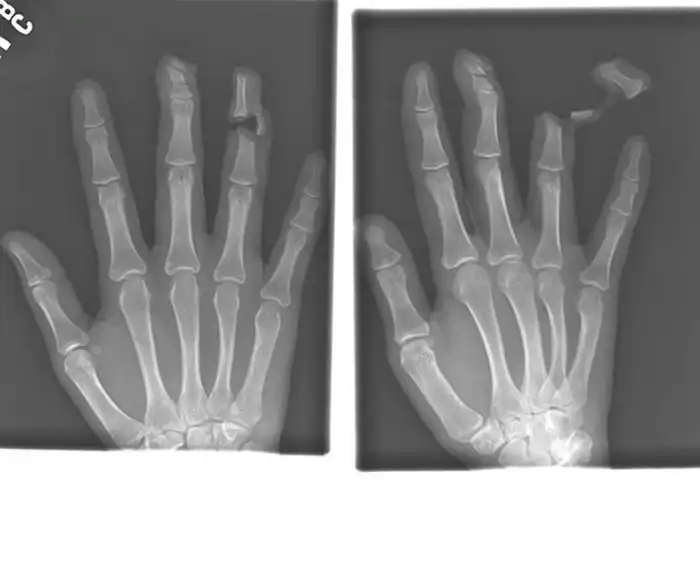

Порой даже не верится, с какими странными и необычными повреждениями в травматологию могут поступить пострадавшие. Всю эпичность профессии врачей травматологии могут с легкостью подтвердить рентгеновские снимки.